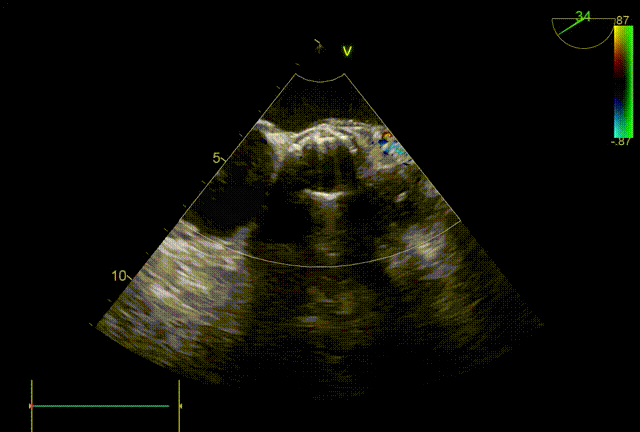

术后即刻TEE

主动脉瓣短轴切面

主动脉瓣长轴切面

术后即刻TEE示:主动脉瓣膜峰值血流速为1.2m/s,最大压差为5mmHg,平均压差为2mmHg。未见明显人工主动脉瓣反流及瓣周漏。